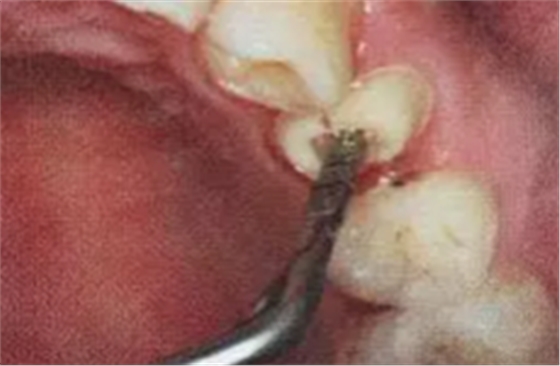

(超聲去除根管殘留物)

通常此時(shí)以超聲潔牙機(jī)更換較細(xì)工作尖進(jìn)入根管(根管消毒沖洗液配合清潔工作后面會(huì)提到),徹底去除樁道根管壁上的附著殘留物,效果明顯。再配合X線片、根管顯微鏡輔助檢查清理的情況下更佳。